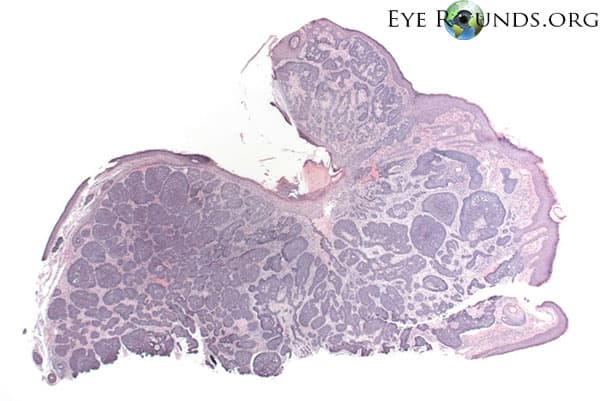

Clinical Images

High-resolution clinical photographs showing various presentations of malignant melanoma of the choroid.